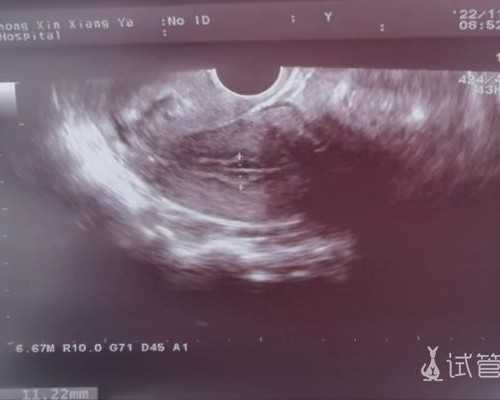

开心啊,我竟然助孕了,现在还看不太清楚,今天上午去医院抽了血,下午去拿结果。